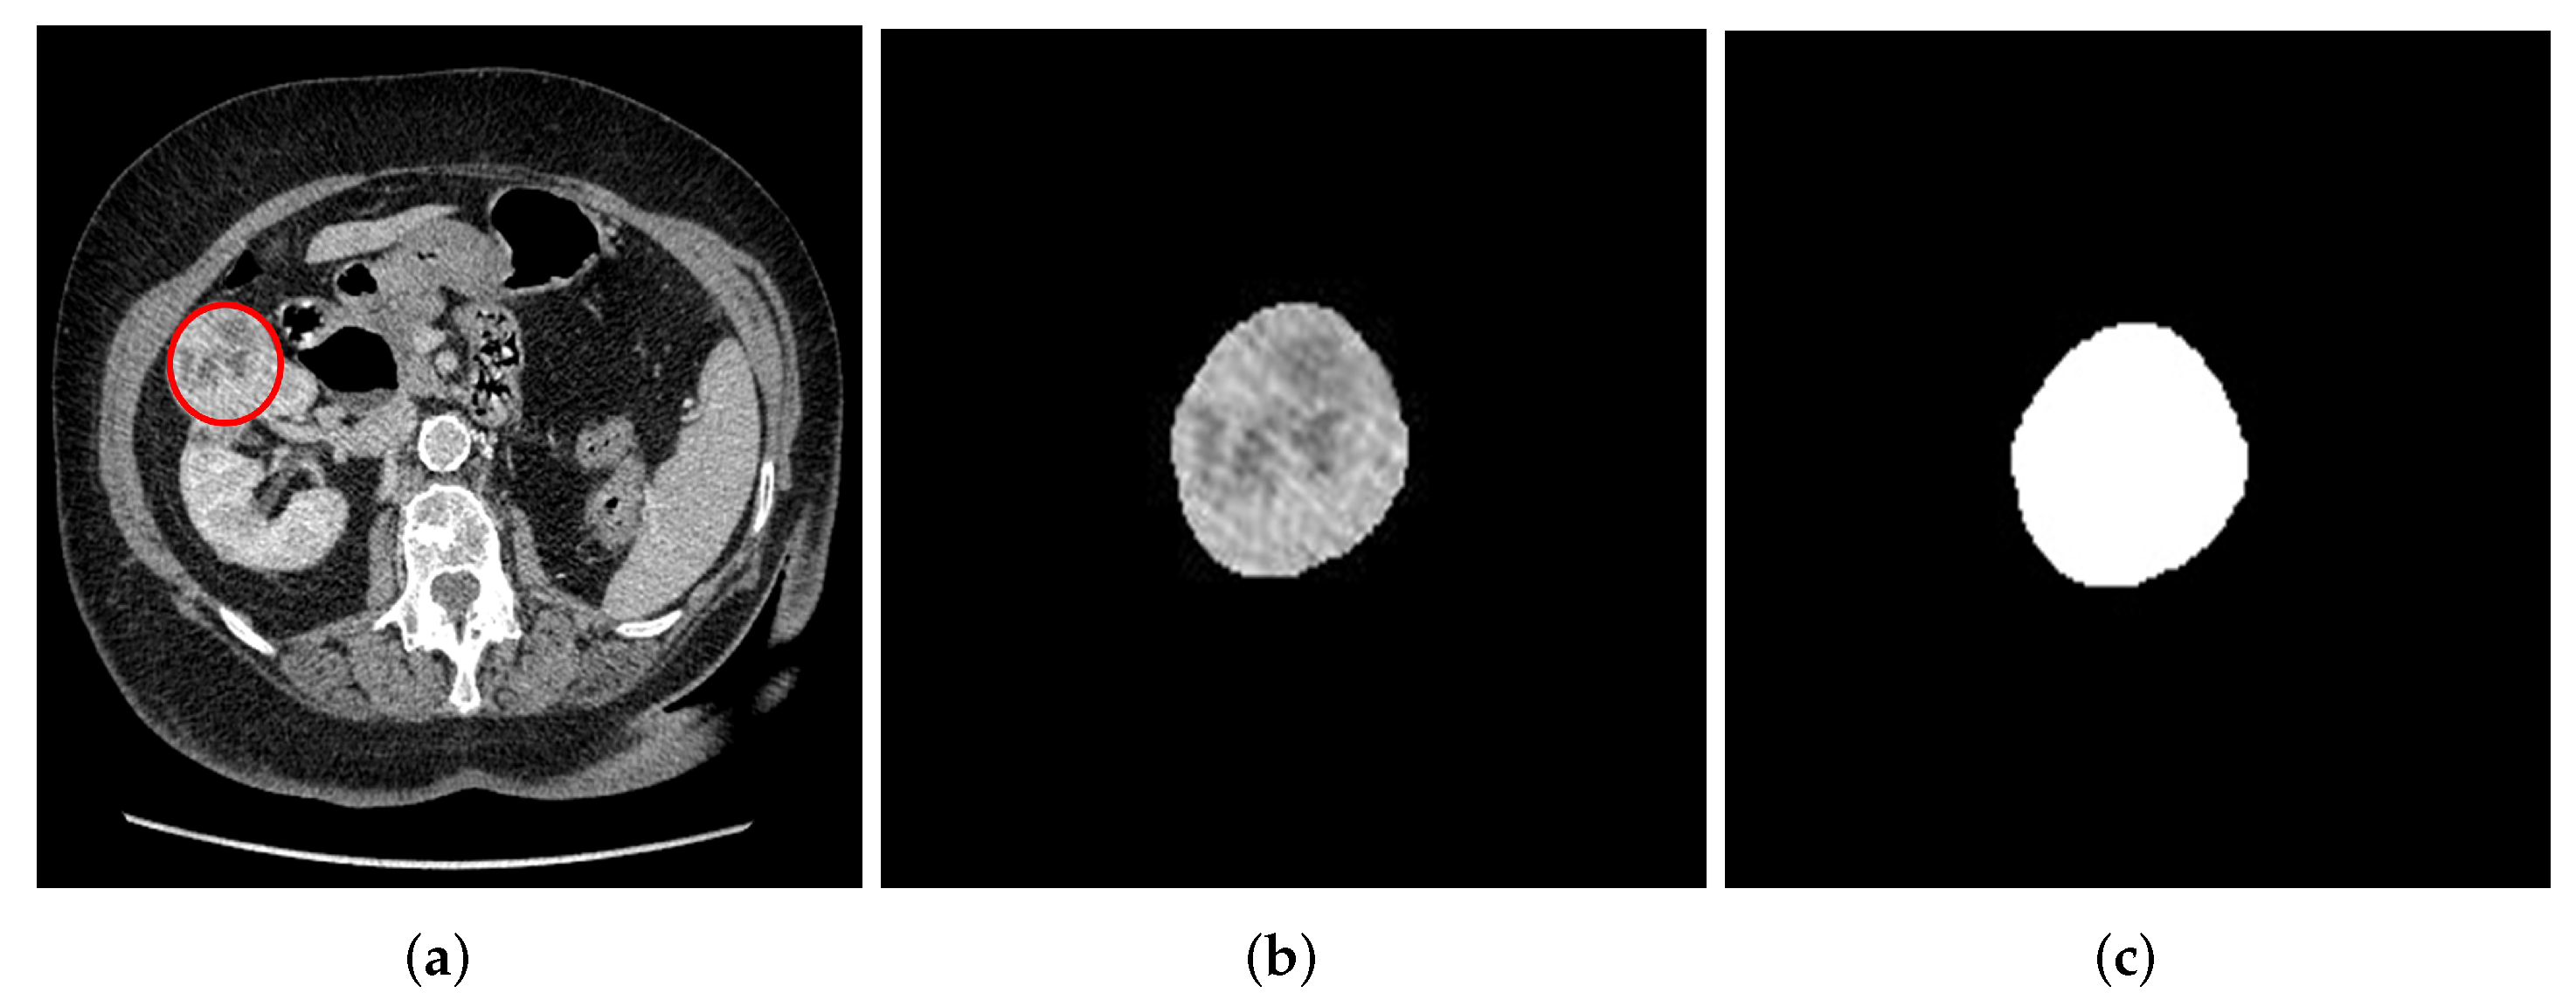

Finally, 3D volume of interest (VOI) segmentation was done semi-automatically using the Slicer 3D software version 4.11, where the VOI was automatically generated after segmenting the first few slices. The 3D segmentation was done as shown in Figure 2. Both 2D and 3D segmentations were performed by a blinded experienced investigator (A.A) delineating the ROI about the edges of the tumors without prior knowledge of the patient’s condition. After that, the segmented masses were revised and confirmed by an experienced urological surgical oncologist (G.N), who further took into consideration the notes of histology and radiology reports. The study used the histopathological assessment after biopsy or nephrectomy as the gold standard.

Figure 2. Semi-automatic 3D slice tumor segmentation using the volume editor of the slicer 3D software. (a) Original axial plane of the 3D image with VOI. (b) Segmented axial tumor plane mask from the kidney. (c) Segmented tumor mask of coronal plane. (d) Segmented tumor mask of sagittal plane. (e) 3D segmentation volume mask.